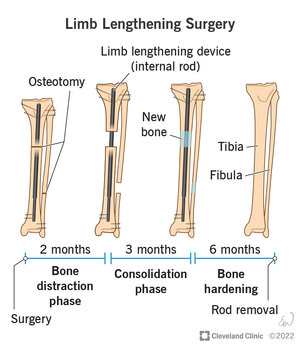

Limb lengthening? Maybe all together if I get really lucky I can be a light light chadlite or HTN.

Limb lengthening? Maybe all together if I get really lucky I can be a light light chadlite or HTN.